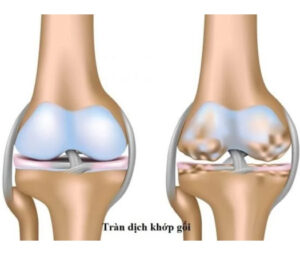

Phục hồi chức năng bệnh lý cơ xương khớp